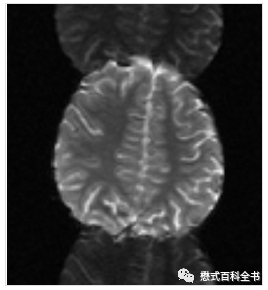

图12~14:非线性梯度的表现

这种图像非常好识别,就是图像变形、扭曲。

出现这种伪影就必须请工程师来检测梯度和调试。